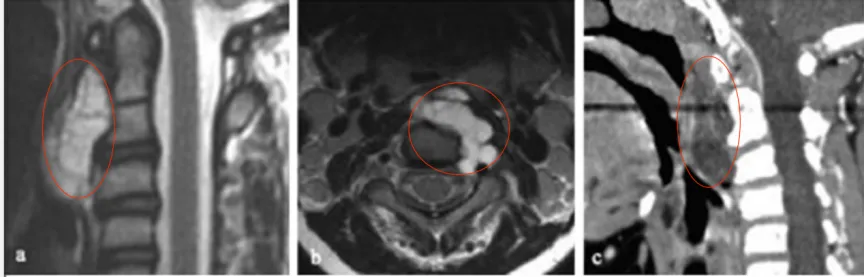

10岁的小凡总是感到头晕,后颈也时常疼痛,父母起初以为是孩子坐姿不正确导致的颈椎病,但紧随其后的,是复发性咽喉感染和吞咽困难。意识到事情不对的父母赶紧带小凡去医院检查,这才终于揪出这个早已藏身多时的“恶魔”——C1-C3脊索瘤,同时还导致上呼吸道压迫,病情十分严重。

无论是脊髓肿瘤还是脊索瘤,治疗的第一步,都是手术切除。鲁特卡教授为小凡进行了经口、经腭、经下颌入路的次全切除术。术后MR显示肿瘤切除达95%以上,C2-C3神经孔内有少量残留肿瘤。

此时,治疗来到了第二步——个体化放疗。结果显示小凡对70gy光子放疗反应良好,幸运的是,孩子的耐受性也很好,治疗十分顺利,放疗后的残留病变明显变小,也无明显放疗副作用。